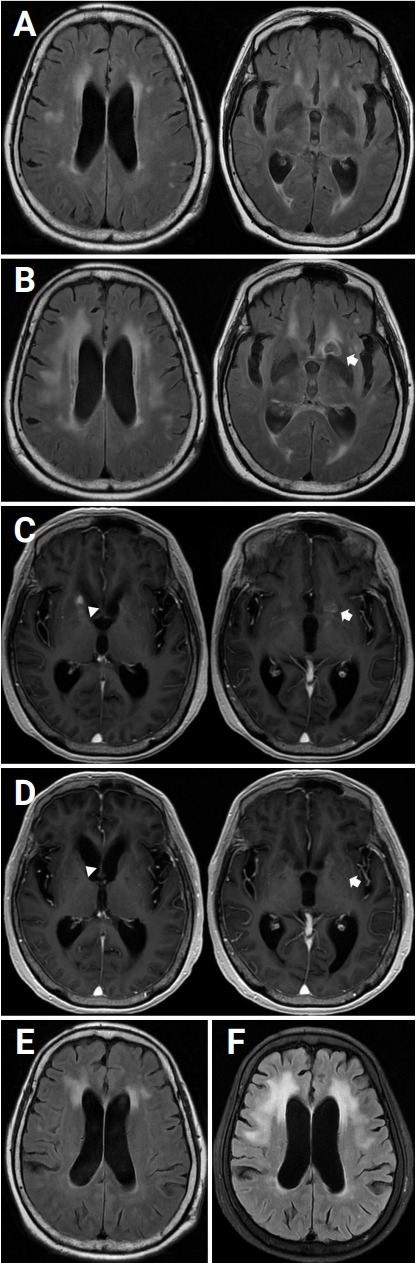

Chronic meningitis may present with clinical features related to hydrocephalus. We report a 76-year-old female who presented to an outpatient clinic with cognitive decline and gait disturbance with recurrent falls. The initial diagnosis of normal pressure hydrocephalus (NPH) was based on the clinical symptoms and magnetic resonance imaging (MRI) of the brain, which showed ventriculomegaly without an obstructive lesion. During follow-up, however, there was remarkable cognitive decline, and she was unable to walk without assistance. Lumbar puncture and brain MRI showed respective lymphocyte-dominant pleocytosis that was positive for cryptococcal antigen and a new encapsulated abscess-like lesion in a left caudate head. Treatment for cryptococcal meningitis was initiated, and the patient was cured after a long treatment with an antifungal agent. As chronic meningitis could be misdiagnosed as NPH, differential diagnoses of etiologies that can cause hydrocephalus should be addressed.